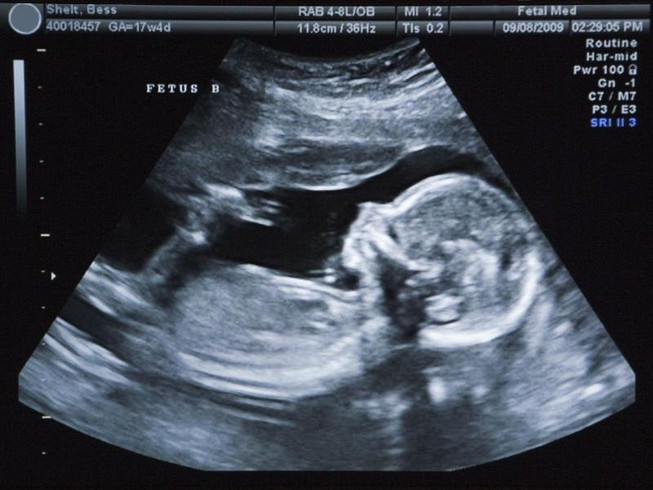

Siêu âm có thể giúp chẩn đoán sớm tình trạng khối u từ trong bụng mẹ. (Ảnh minh họa)